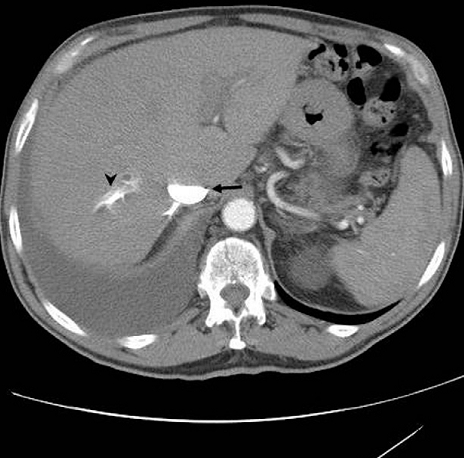

74 ¼¼ ³²È¯

¿ì¿¬È÷ Rt pleural effusion °üÂûµÇ¾î ³»¿øÇÔ

5´Þ Àü¿¡ ¹ß¿­°ú ¿ÀÇÑ ±âħÀ» µ¿¹ÝÇϴ ȣÈí±âÁõ»óÀÌ ¸î ÁÖµ¿¾È Áö¼ÓµÇ¾ú°í ±âħÀº È£ÀüµÇ¾úÀ¸³ª ¿òÁ÷À϶§ÀÇ ¼ûÂ÷´Â Áõ»óÀº¾ÆÁ÷ ³²¾Æ ÀÖÀ½

Pleural uid analysis:

a LDHlevel of 50 IU/L (pleural uid/serum ratio, 0.40);

total protein level, 3.5 mg/dL (pleural uid/serum ratio, 0.49);

glucose level, 112 mg/dL.

Pleural uid cytology was negative for malignancy